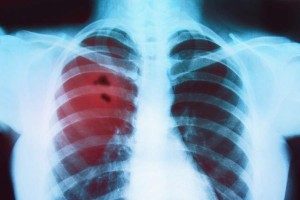

Bronchitis

30-09-2014 | 2150 View(s)

Bronchitis is an inflammation of the mucous membranes of the bronchi (the larger and medium-sized airways that carry airflow from the trachea into the more distal parts of the lung parenchyma). Bronchitis can be divided… Read more...